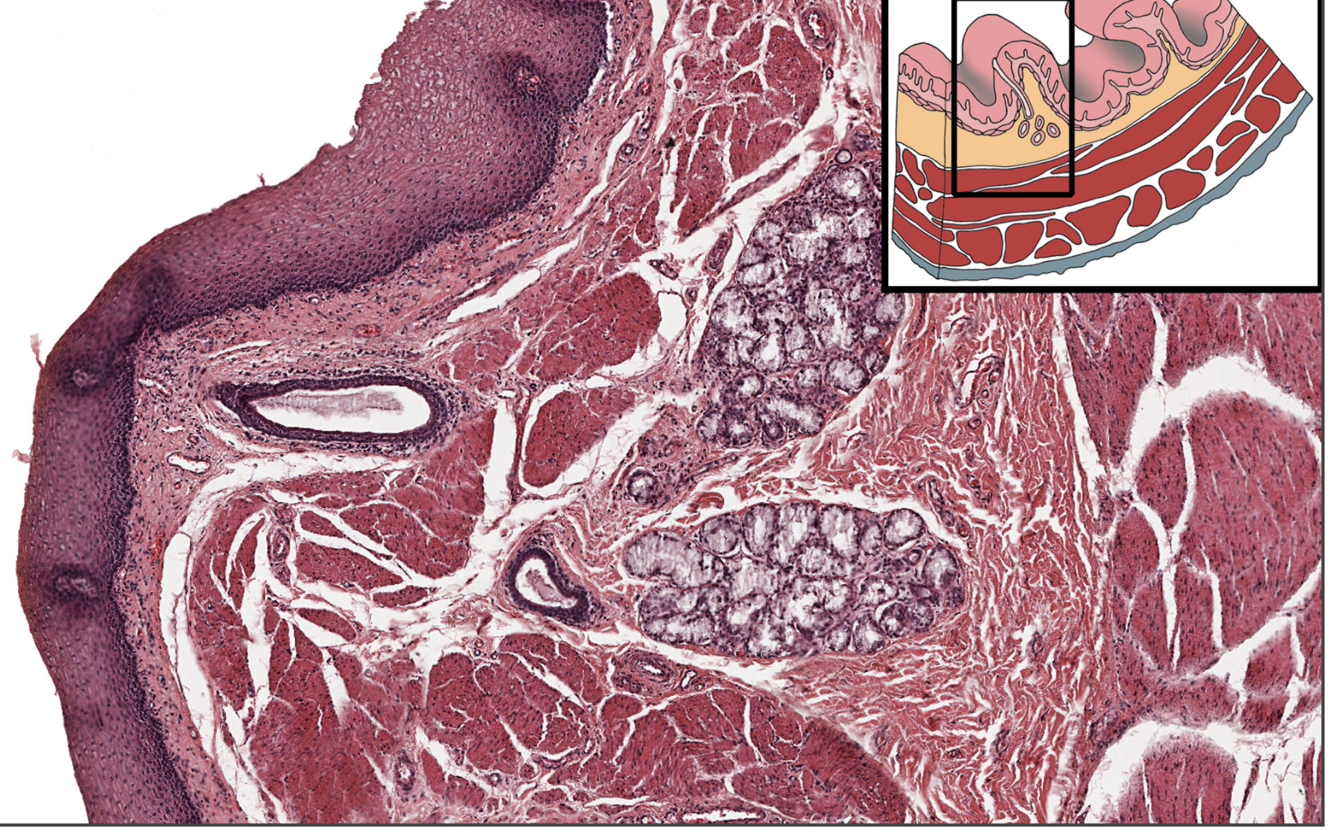

Q

what is this

A

It is the oesophagus -